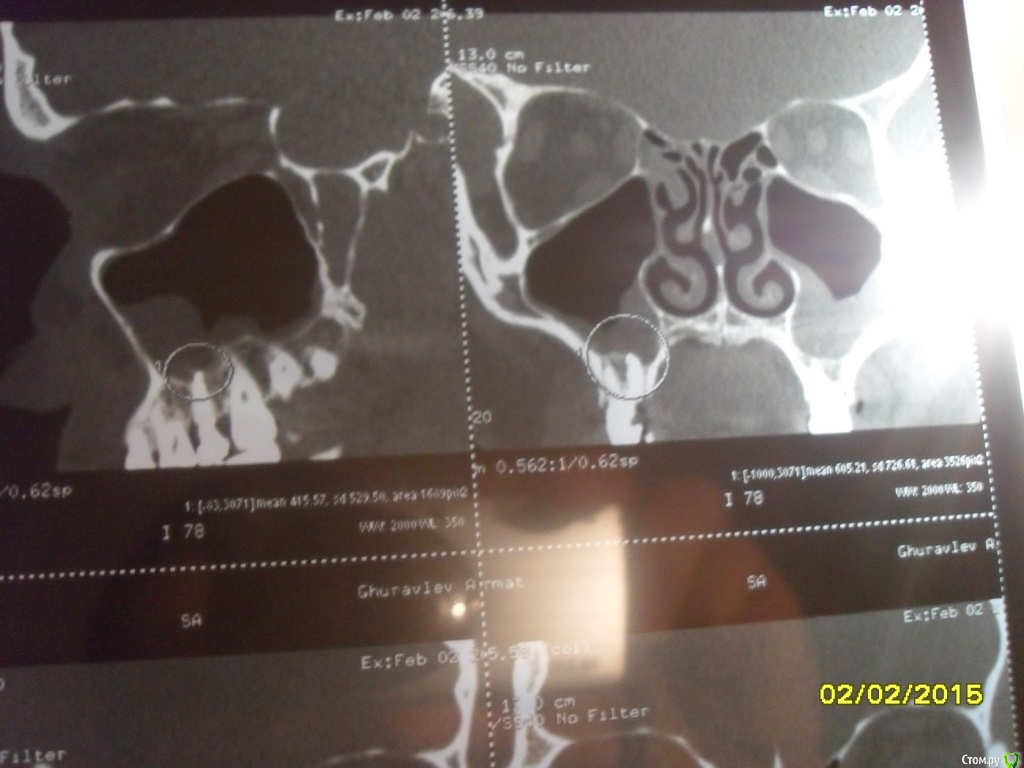

asin Опубликовано 7 февраля, 2015 Поделиться Опубликовано 7 февраля, 2015 (изменено) Добрый день всем, прошу у вас помощи или совета. Ездил на МСКТ пазух носа нашли пломбировочный материал, сломанный инструмент и кисту в правой пазухе 5 зуб. у меня его делали там штифт стоит канал пломбирован((((( мучает хронический катаральный гайморит((((( снимки прилагая может быть подскажите что мне делать.советуют дергать зуб с корнем и потом ушивать потому что откроется вход в пазуху....https://yadi.sk/d/nfWCumo7eU5ST тут образ диска МСКт... если кто то посмотрит буду признателен Изменено 7 февраля, 2015 пользователем asin Ссылка на комментарий

asin Опубликовано 16 февраля, 2015 Автор Поделиться Опубликовано 16 февраля, 2015 (изменено) надо дентальное КТ сделать, тогда будет ясно есть ли шанс перелечить зуб. Ну или сразу удалить.по рекомендации ЧЛХ удален зуб снимок прилагаю. я так понимаю пломб. мат остался.перфорация не нарушена. какую операцию рекомендуете Изменено 16 февраля, 2015 пользователем asin Ссылка на комментарий

asin Опубликовано 28 апреля, 2015 Автор Поделиться Опубликовано 28 апреля, 2015 планируется операция 1.Операция на верхнечелюстной пазухе (с применением радионожа "Surgitron", бормашины, (эндоскопически ) - удаление пломб материала2. Подслизистая коррекция перегородки носа с применением радионожа "Surgitron" расширение левого соустья и прижигание слизистой отсюда вопрос, как сложно будет достать материал именно оттуда где он лежит? Ссылка на комментарий